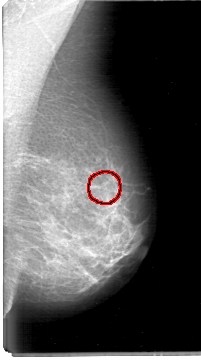

D_4054_1.LEFT_MLO

LEFT_MLO LINES 5386 PIXELS_PER_LINE 3001 BITS_PER_PIXEL 12 RESOLUTION 43.5 OVERLAY

FILE: D_4054_1.LEFT_MLO.OVERLAY

TOTAL_ABNORMALITIES 1

ABNORMALITY 1

LESION_TYPE CALCIFICATION TYPE MILK_OF_CALCIUM DISTRIBUTION CLUSTERED

ASSESSMENT 0

SUBTLETY 3

PATHOLOGY BENIGN

TOTAL_OUTLINES 1